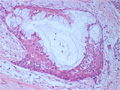

Macroscopic finding:A well-demarcated solid tumor lies in the parotid gland. The cut surface of this tumor is yellowish-white with focal glistening areas. The glistening areas correspond to abundant myxomatous or chondroid stroma.